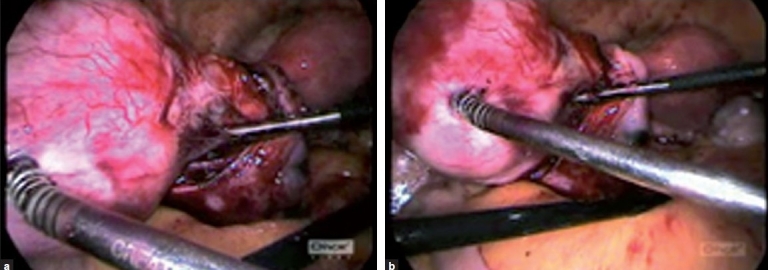

手术治疗真阔韧带肌瘤2例,假阔韧带肌瘤30例。所有的都是通过腹腔镜切除的,出血量很少,也不需要输血。我们对所有病例的输尿管轨迹进行了追踪。没有出现并发症。

Two cases of true broad ligament fibroids and thirty cases of false broad ligament fibroids were operated. All were removed through the laparoscopic route, with very minimal blood loss and without a need for blood transfusion. We traced the course of the ureters in all cases. No complications were met with.